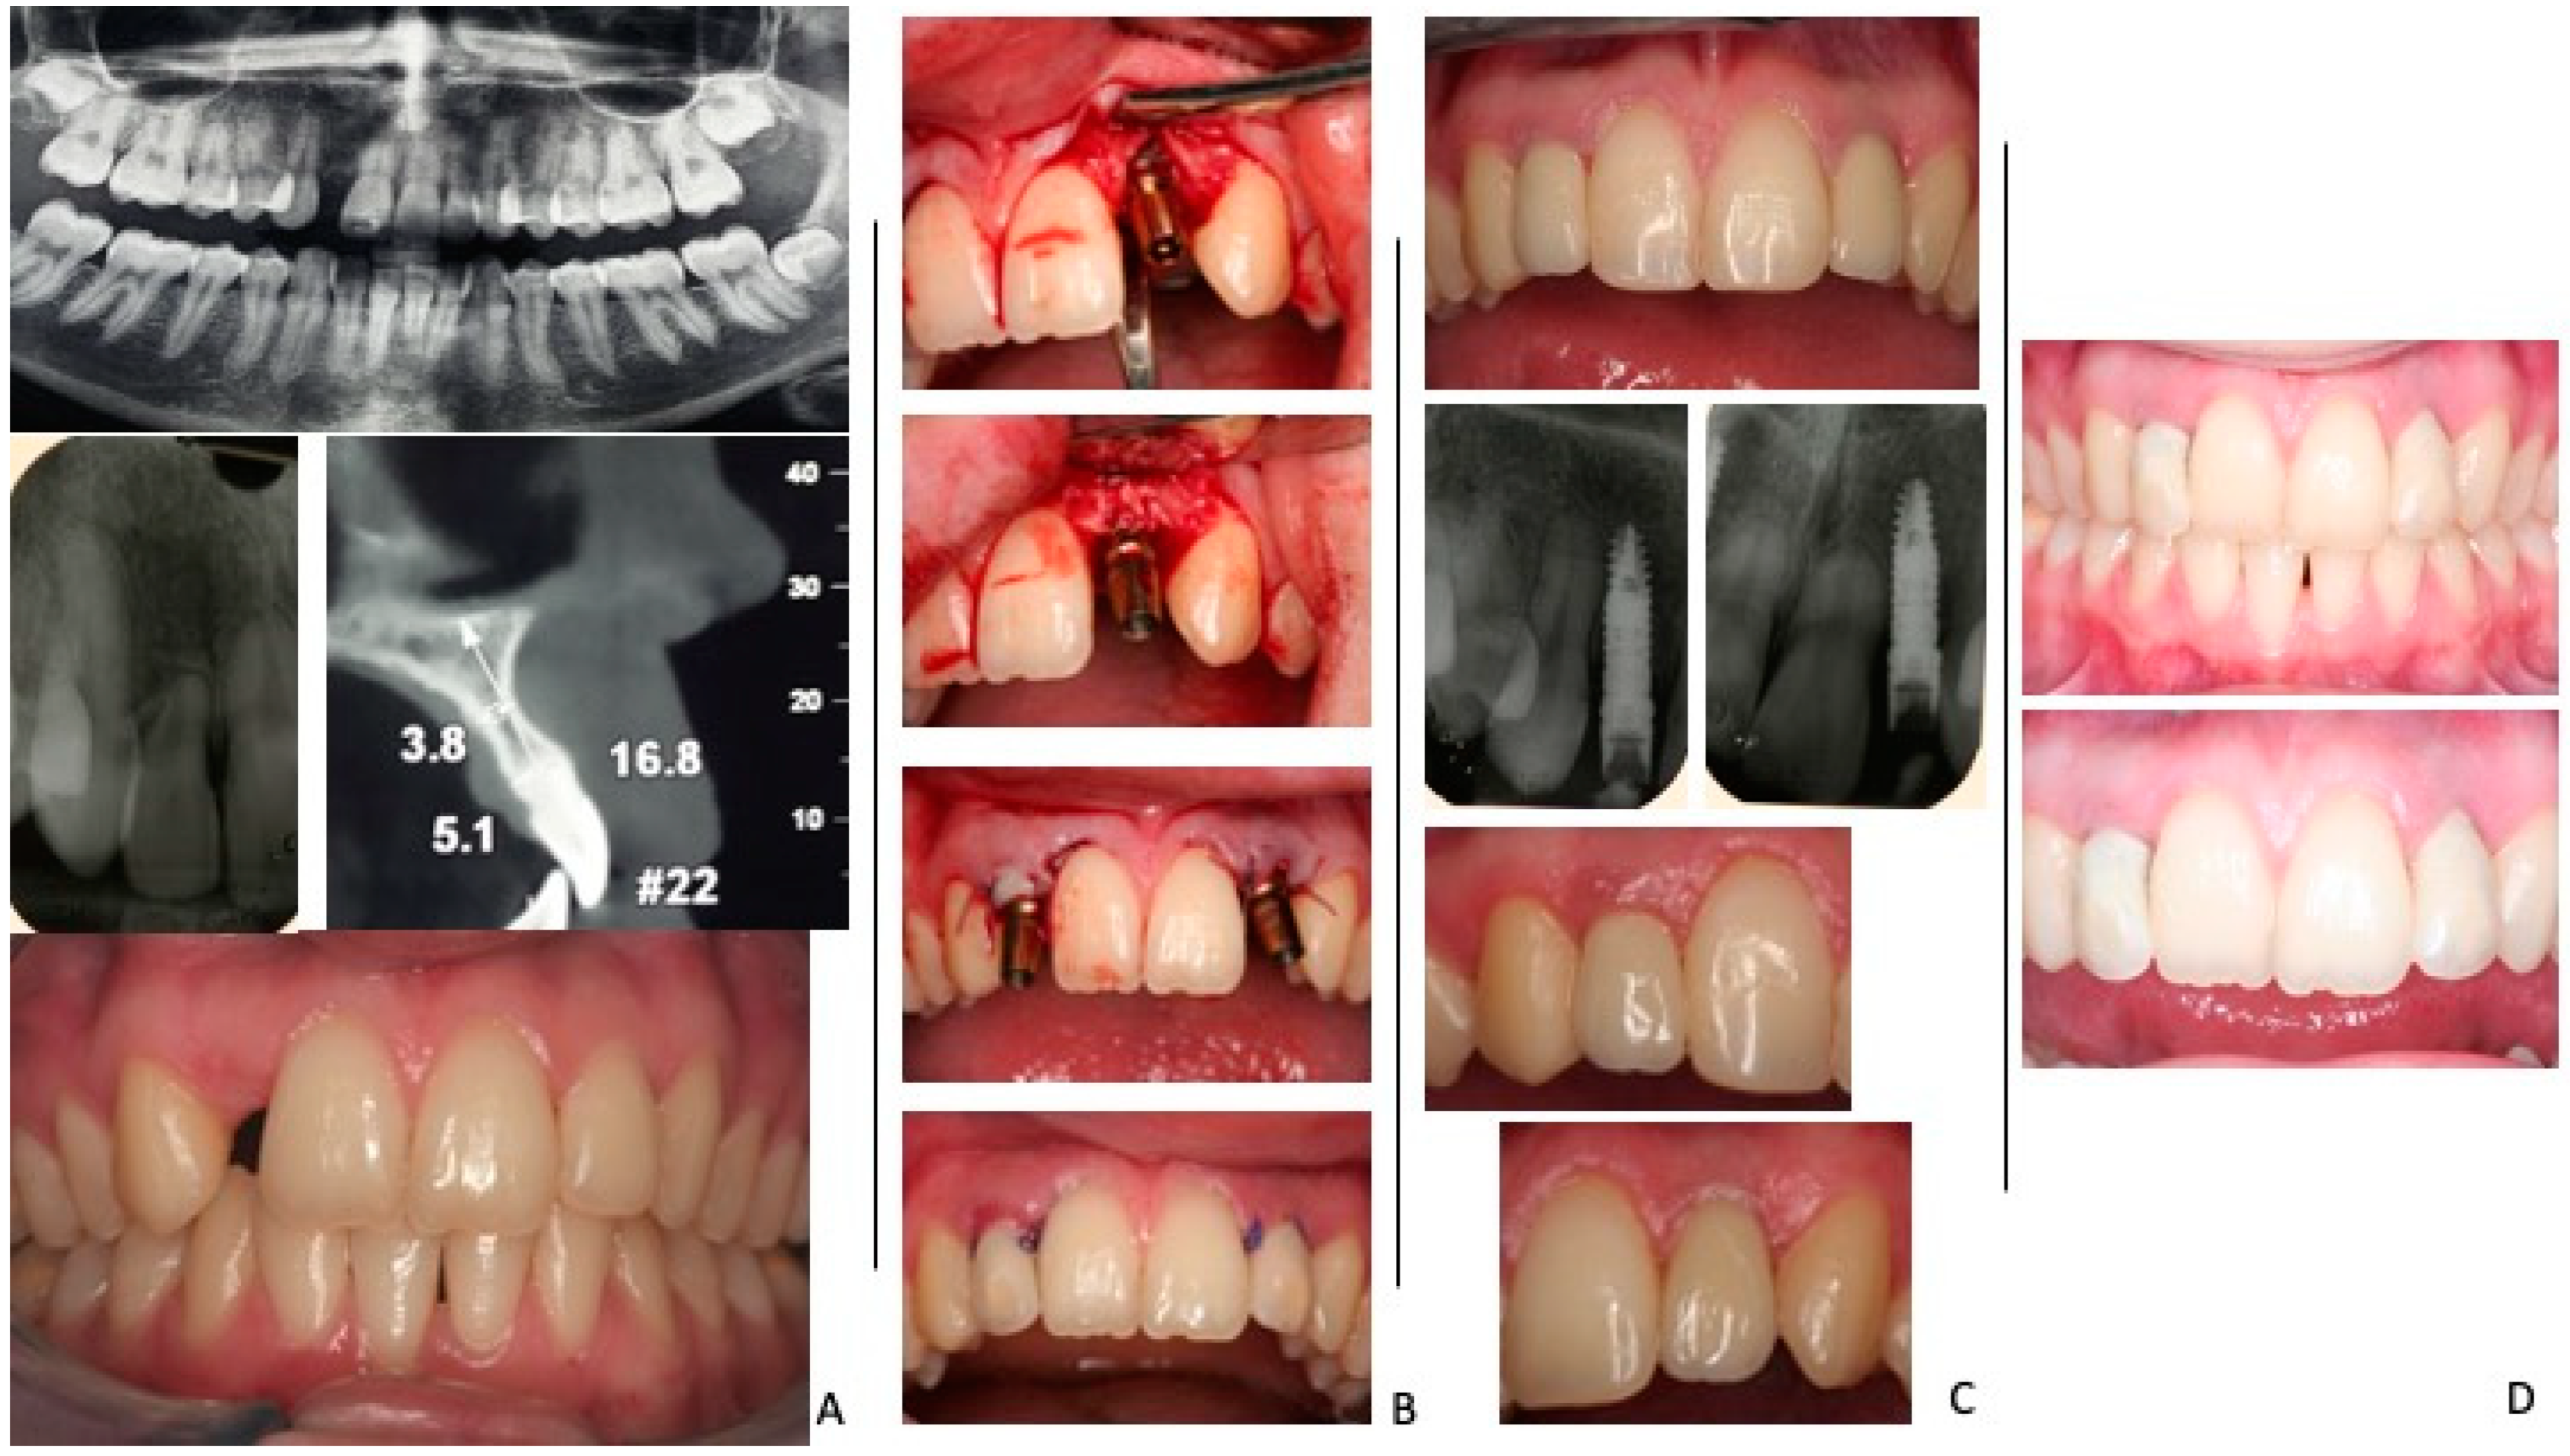

- Lanza, A.; Scognamiglio, F.; Femiano, F.; Lanza, M. Immediate, Early, and Conventional Implant Placement in a Patient with History of Periodontitis. Case Rep. Dent. 2015, 2015, 217895. [Google Scholar] [CrossRef]